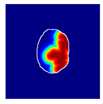

| True label: Mesangioproliferative |  |  |  |  |  |

| single-multiclass: Mesangioproliferative p = 0.935, IoU = 0.029 | |||||

| multiple-binary: Mesangioproliferative p = 0.988, IoU = 0.032 | |||||

| spatially guided: Mesangioproliferative p = 0.873, IoU = 0.201 |